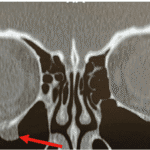

The “Not So Easy” Orbital Floor Fracture Case

The “Not So Easy” Orbital Floor Fracture Case

by Joseph Muscente, OD, MS, FAAO | May 26, 2025 | Surgical, Volume 3, Issue 2 | 0 |

Clinical approach to orbital fractures or potential orbital fractures should always include imaging (maxillofacial CT), visual acuity testing, pupil...